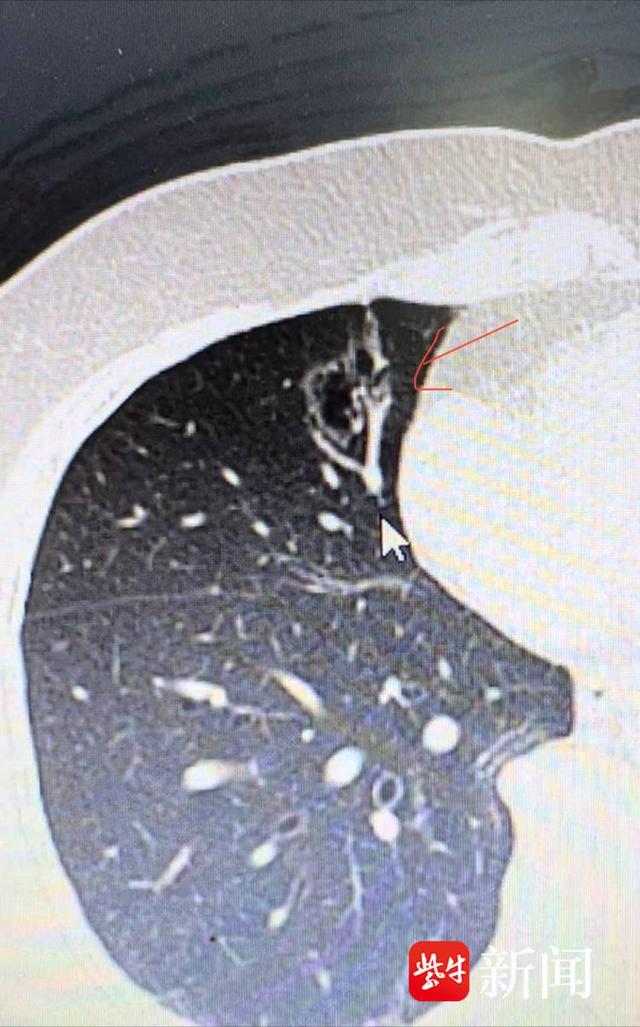

陈爷爷肺部ct片

肉芽肿和异物后,之前杨红肺部的白色肿块影像消失(见红色圈内部分)